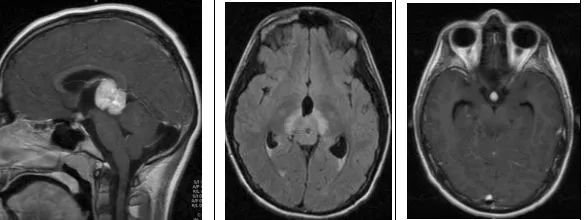

影像特征

矢状位及横断位T1WI+C示松果体区明显强化肿块,鞍上也可见小的强化肿块;横断位T2WI+FLAIR示松果体区高信号肿块伴周围水肿。